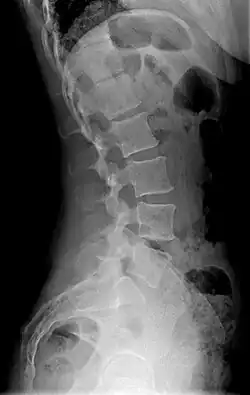

| Diagram showing normal curvature (posterior concavity) of the cervical (neck) and lumbar (lower back) vertebral column (spine) | |

Precise diagnosis is done by looking at a complete medical history, physical examination, and other tests of the patient. X-rays are used to measure the lumbar curvature. On a lateral X-ray, a normal range of the lordotic curvature of between 20° and 60° has been proposed by Stagnara et al., as measured from the inferior endplate of T12 to the inferior endplate of L5.[18] The Scoliosis Research Society has proposed a range of 40° and 60° as measured between the upper endplate of Th12 and the upper endplate of S1.[18] Individual studies, although using other reference points, have found normal ranges up to approximately 85°.[18] It is generally more pronounced in females.[18] It is relatively constant through adolescence and young adulthood, but decreases in the elderly.[18]